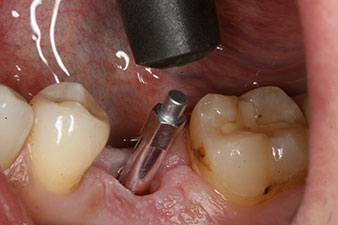

Implantat

Figura 3: Después de realizar la preparación con el motor de implantes Implantmed, se enroscó mecánicamente un implante (diámetro 4 mm, longitud 12 mm) con un torque de 43 Ncm.

Tras la extirpación minuciosa del tejido de granulación, se incorporó el implante tal como se había planificado (blueSky, bredent).